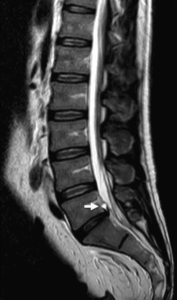

Irudi froga batek, erradiografia zein erresonantzia magnetikoak, gorputzeko egituren eta ehunen ( hezurra, muskulua, nerbioa zein erraiak) egoera fisikoaren berri ematen du soilik. Baina ezin dugu ahaztu, aurrean daukagun pertsonak mina zein beste estimulu askoren pertzepzioa jaso eta interpretatzeko gai den nerbio sistema konplexua daukala. Irudi batek ez du minaren intentsitatea, kokapena eta motaren inguruko informaziorik emango, ezta pertsona horrek sentitzen dituen emozioen, bere hezkuntza eta ulergarritasun mailaren berri emango.

Oro har, irudi frogetan azaltzen diren aztarnak, gorputzak adin konkretu batetik aurrera jasaten dituen aldaketa fisiologikoak dira, hau da, berezkoak eta naturalak.